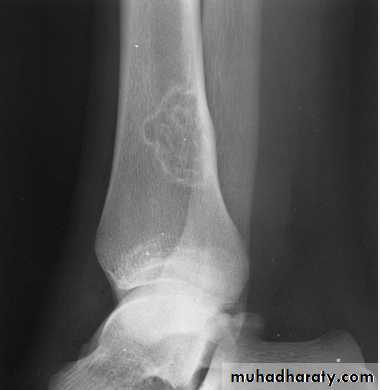

Q….lytic, expansile lesion, Sub articular in location, Not clearly defined margin with thinning of the cortex ???

Giant cell tumor

The sign & findingsWide zone of transition is being

Elevation of the periosteum at the side of the tumor marginlytic, expansile lesion, Sub articular in location give the soap bubble appearance